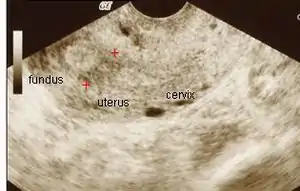

| تصویر اولتراسونیک | |